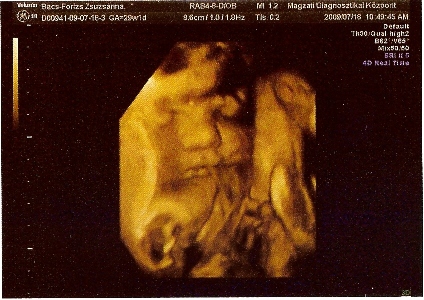

Megkérdezte, hogy hányat tettünk vissza? Én mondtam, hogy múlt héten egy volt. A férjem fogta fel a kérdést és válaszolta, hogy 3-at. Én annyira féltem, hogy nem él, hogy nem is tudtam koncentrálni. Erre Ö azt mondta, hogy itt vannak. Fel sem fogtam, nem akartam elhinni. A férjemet figyeltem, aki egyre sápadtabb volt. Kérdeztem, hogy mind a három? Élnek? A 17x17mm-es petezsákomban 5,2mm CTL méretű baba van szuper erős szívhanggal, annyira jó volt hallgatni, azóta is csak arra tudok gondolni. A 15x15mm-es petezsákban még csak lüktetős szívecske van, de ott is szép szikhólyag mint az előzőnél, és van még egy 9x9mm-es petezsákom, amiben baba még nem látszik, de azt mondta V.-doki, hogy ő sokáig vándorolt és csak nemrég ágyazódott be, jövő keddre kiderül, hogy mi van vele.

Próbálok feltenni képet, bár csak a mobilommal tudom itt a balcsin lefotózni az uhus képet, így nem lesz jó minőség.